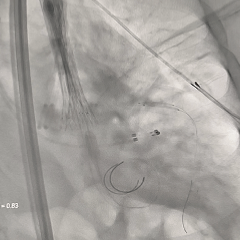

重新调整后重新定位

考虑第一次释放时瓣膜位置偏深,第二次瓣膜定位调整至瓣架底端约为瓣上4-5mm左右

第二次释放至全展开位

瓣膜释放过程中猪尾导管上移,瓣架轻微下移至瓣上2mm左右

全展开位造影评估

瓣架形态可,无窦侧深度约瓣上2mm,小弯侧深度接近零位,瓣架整体贴靠左窦侧,右冠显影正常,左冠显影尚可,可见少量瓣周漏